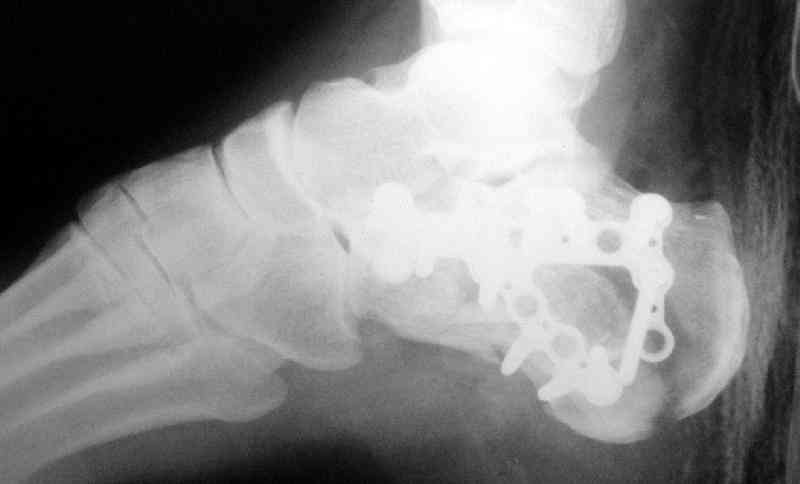

Re: Перелом пяточной кости

послал А.П.Ким 09 Октябрь 2007, 09:41

Открытый и закрытый способы лечения.